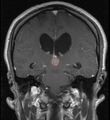

في كثير من الأحيان ، يُعرف شلل الحملقة إالعلوي جنبًا إلى جنب مع العديد من الموجودات العينية مثل رأرأة تراجع التقارب وتراجع الجفن المعروف أيضًا باسم علامة كولير وانفصال الضوء القريب (تتكيف الحدقة مع الضوء ولكنها لا تتفاعل مع الضوء) يسموا كمجموعة بمتلازمة بارينو[1] أو متلازمة الدماغ المتوسط الظهرية ، هي الأعراض الجسدية الوحيدة التي تظهر. يحدث هذا بسبب ضغط مركز الحملقة العمودي في سقف الدماغ المتوسط على مستوى الأكيمة العلوية والعصب القحفي III. يتضمن العمل عادةً التصوير العصبي كما يظهر على اليمين.[citation needed]